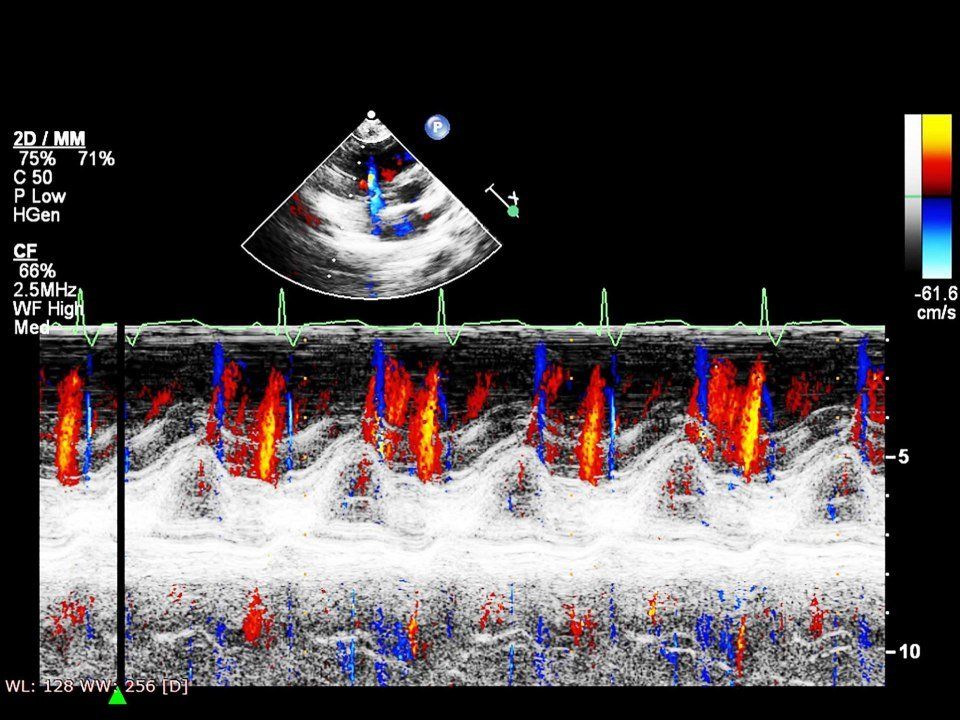

Ecocolor doppler